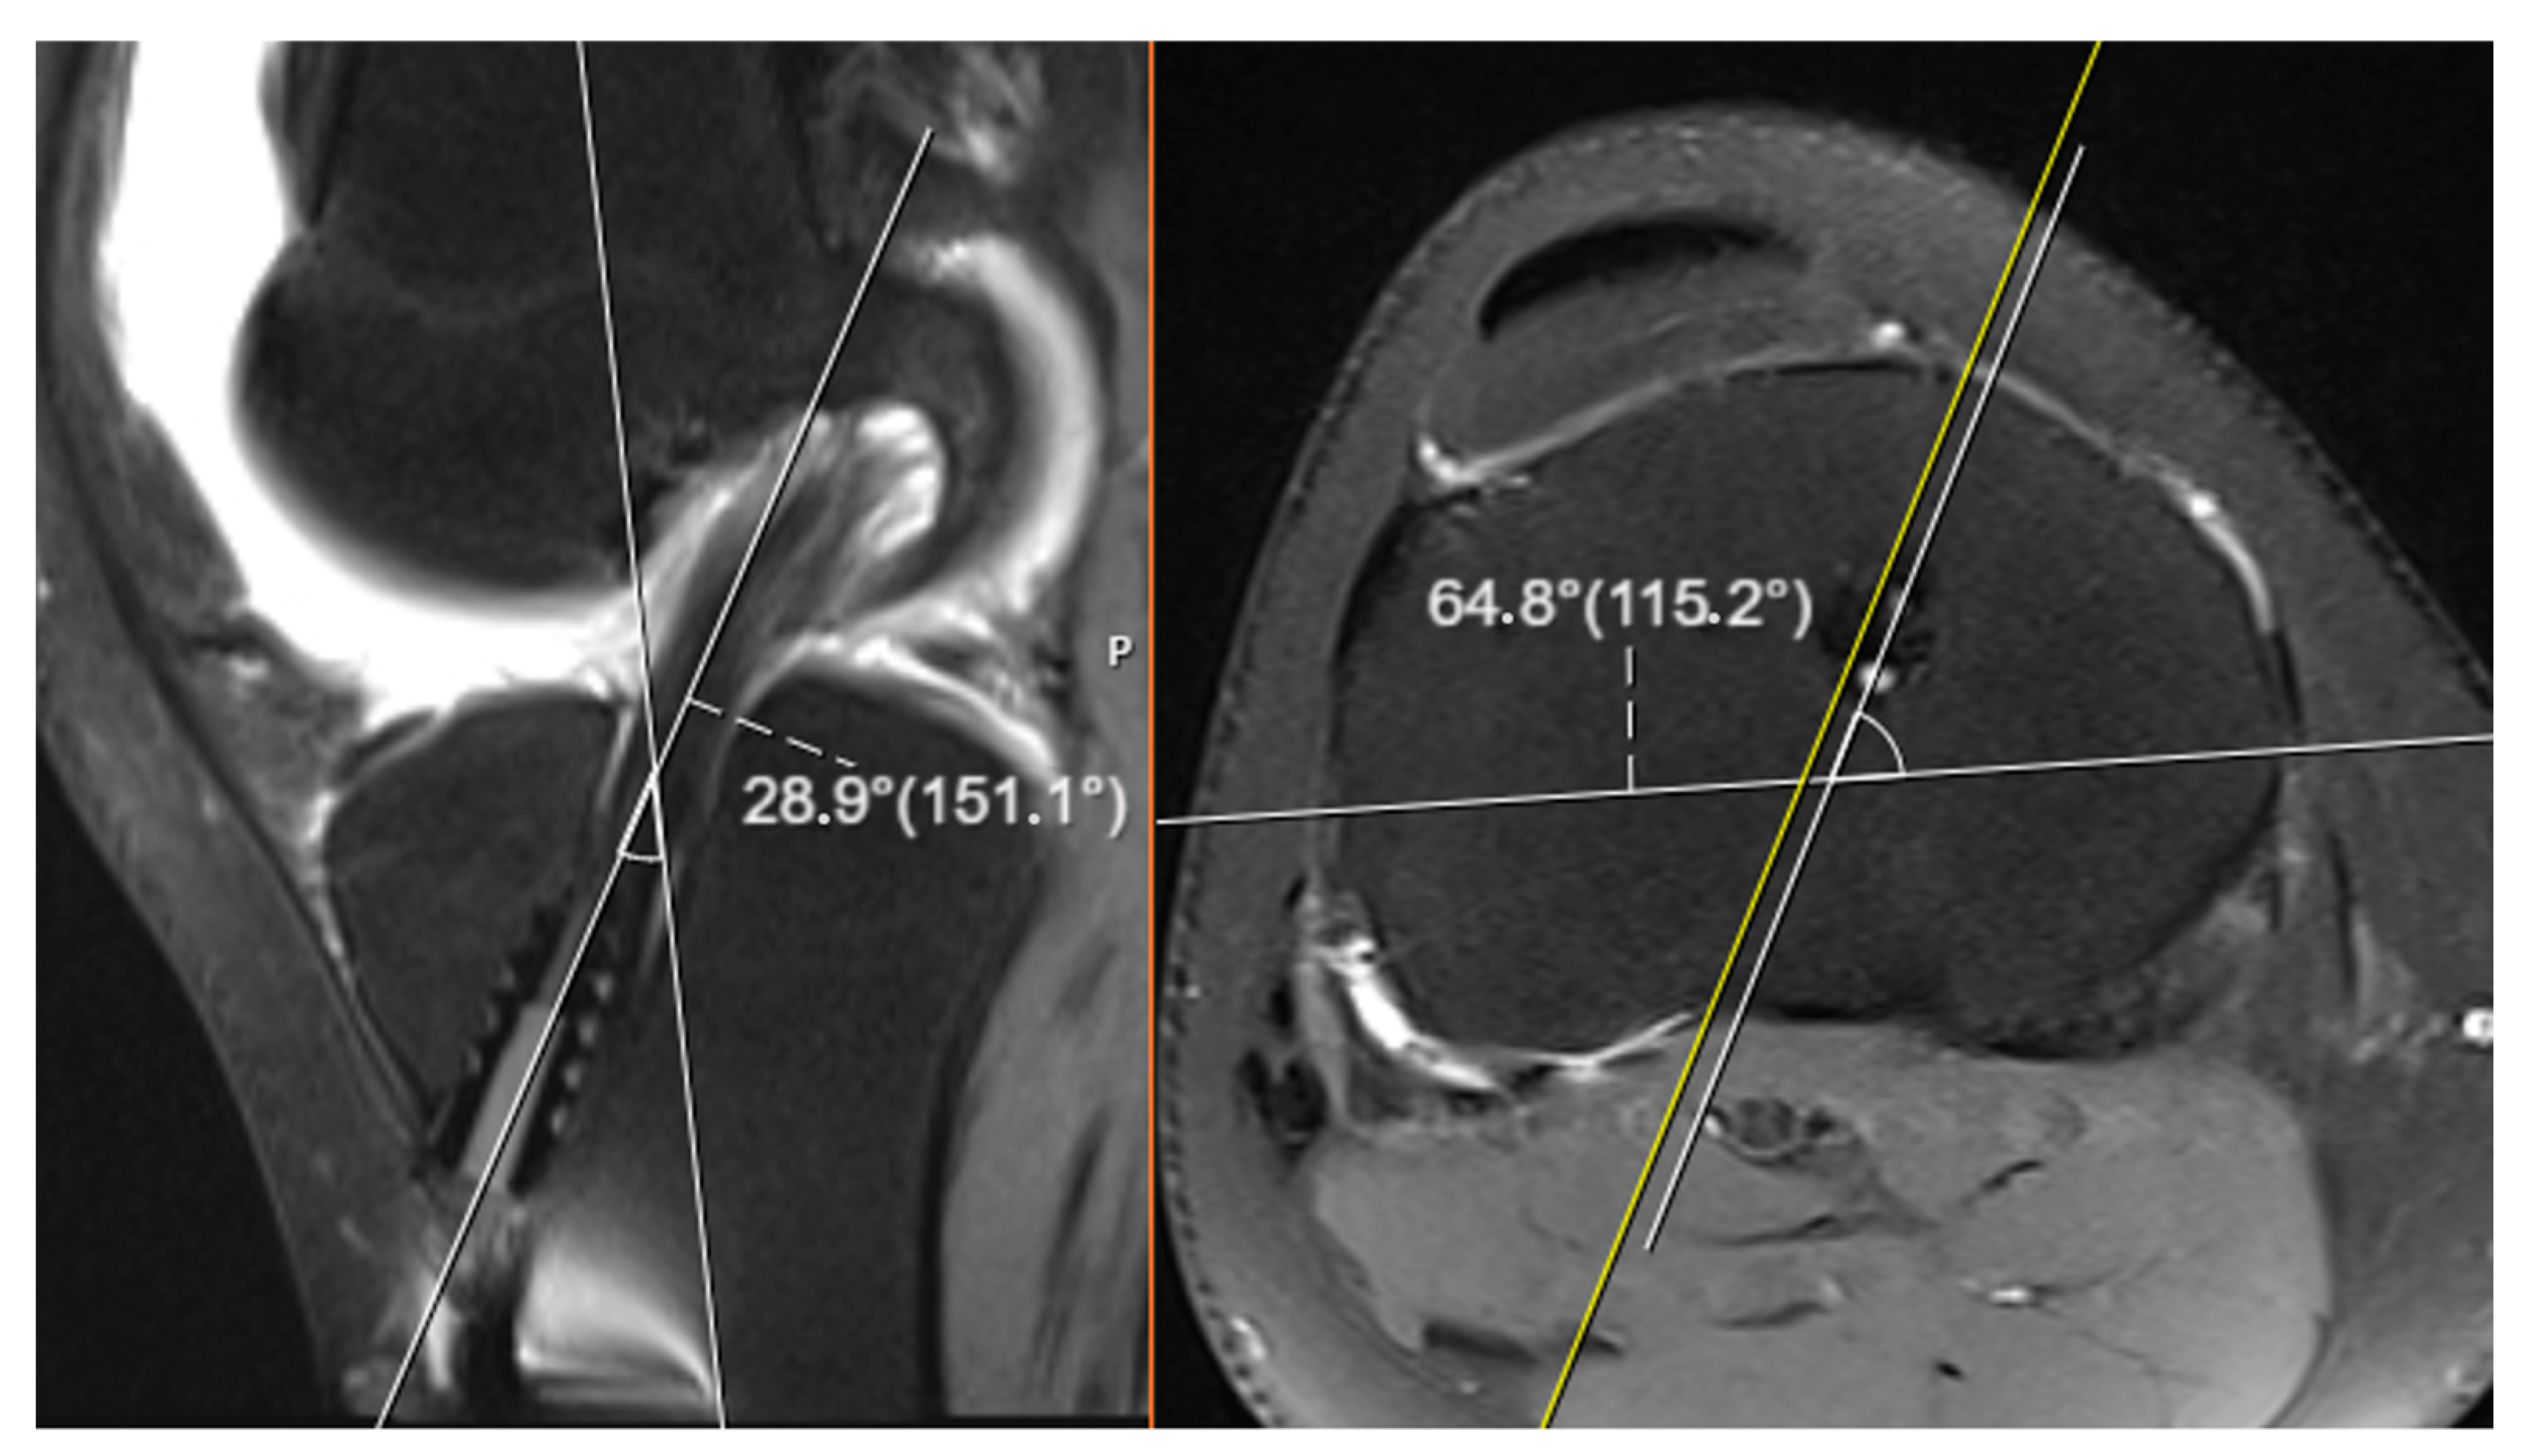

For each patient, angular measurements were obtained from both anteroposterior (AP) and lateral knee roentgenograms. On these radiographs, the angle formed between the anatomical longitudinal axis of the tibia and the axis of the tibial tunnel was measured separately for each imaging plane. These two-dimensional angular values were subsequently utilized in a geometric formula to calculate the three-dimensional spatial orientation of the tibial tunnel. The purpose of this process was to estimate the actual tunnel position in a three-dimensional space based solely on the information obtained from standard two-plane radiographic imaging (see Figure 1).

In terms of the anatomical orientation, the AP knee roentgenogram was defined as corresponding to the coronal plane, which provides a frontal view of the knee, while the lateral knee roentgenogram was regarded as representative of the sagittal plane, offering a side profile of the joint. All calculations for the three-dimensional angle estimation were based on these respective planes. This methodological approach allowed the study to simulate a 3D angular perspective using only conventional 2D radiographic images, providing an efficient and accessible alternative to more advanced imaging modalities (see Figure 2).

Figure 1. Image showing the measurement of tunnel angles on knee roentgenograms.